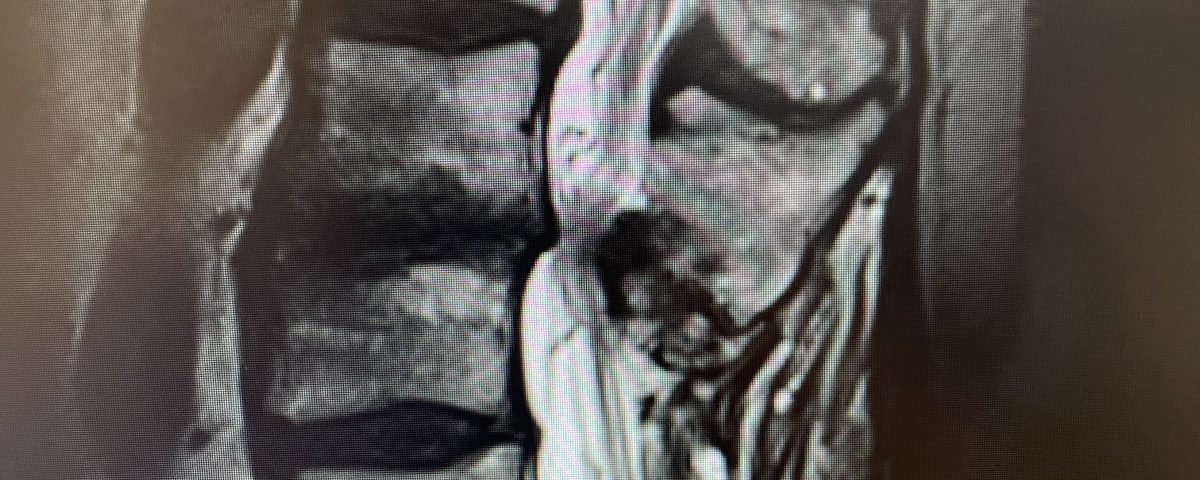

A 69-year-old male presents with chronic low back pain that seems to improve with sitting. The patient had had a prior laminectomy for severe stenosis and in situ fusion five years prior which means that we used bone graft to perform the fusion but no instrumentation. He had done well. Over the last year or so he developed low back pain but no leg pain. The patient had tried all means of conservative management including physical therapy, chiropractic care, acupuncture and epidural injections. Neurologically he was intact. MRI revealed significant stenosis at L2-3 above his prior laminectomy and fusion (Fig 1). We discussed options including surgery. One of the problems we face is a patient with severe stenosis that has severe low back pain with no leg pain. This is particularly challenging when the back pain goes away in flexion or sitting. The quandary is that anecdotally patients with these specific symptoms do tend to improve their back pain after laminectomy, although there are no good studies to support this. Patients with classic neurogenic claudication with pain down their legs when they walk and improved when they sit have a better chance of success. Subjecting a patient to laminectomy for just back pain in the face of having prior surgery puts the patient at risk for not only a potential dural leak because of scarring, but also there may be less of a chance of relieving the back pain than if the patient has leg symptoms. After a discussion, since the patient for the most part is able to manage with conservative treatment modalities is just wait and see over the next three months.